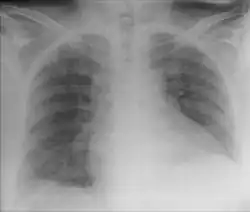

| Chest X-ray showing obvious Chilaiditi's sign, or presence of gas in the right colic angle between the liver and right hemidiaphragm. | |

Chilaiditi syndrome is a rare condition when pain occurs due to transposition of a loop of large intestine (usually transverse colon) in between the diaphragm and the liver, visible on plain abdominal X-ray or chest X-ray.[1]

Normally this causes no symptoms, and this is called Chilaiditi's sign. The sign can be permanently present, or sporadically. This anatomical variant is sometimes mistaken for the more serious condition of having air under the diaphragm (pneumoperitoneum) which is usually an indication of bowel perforation, possibly leading to surgical interventions.